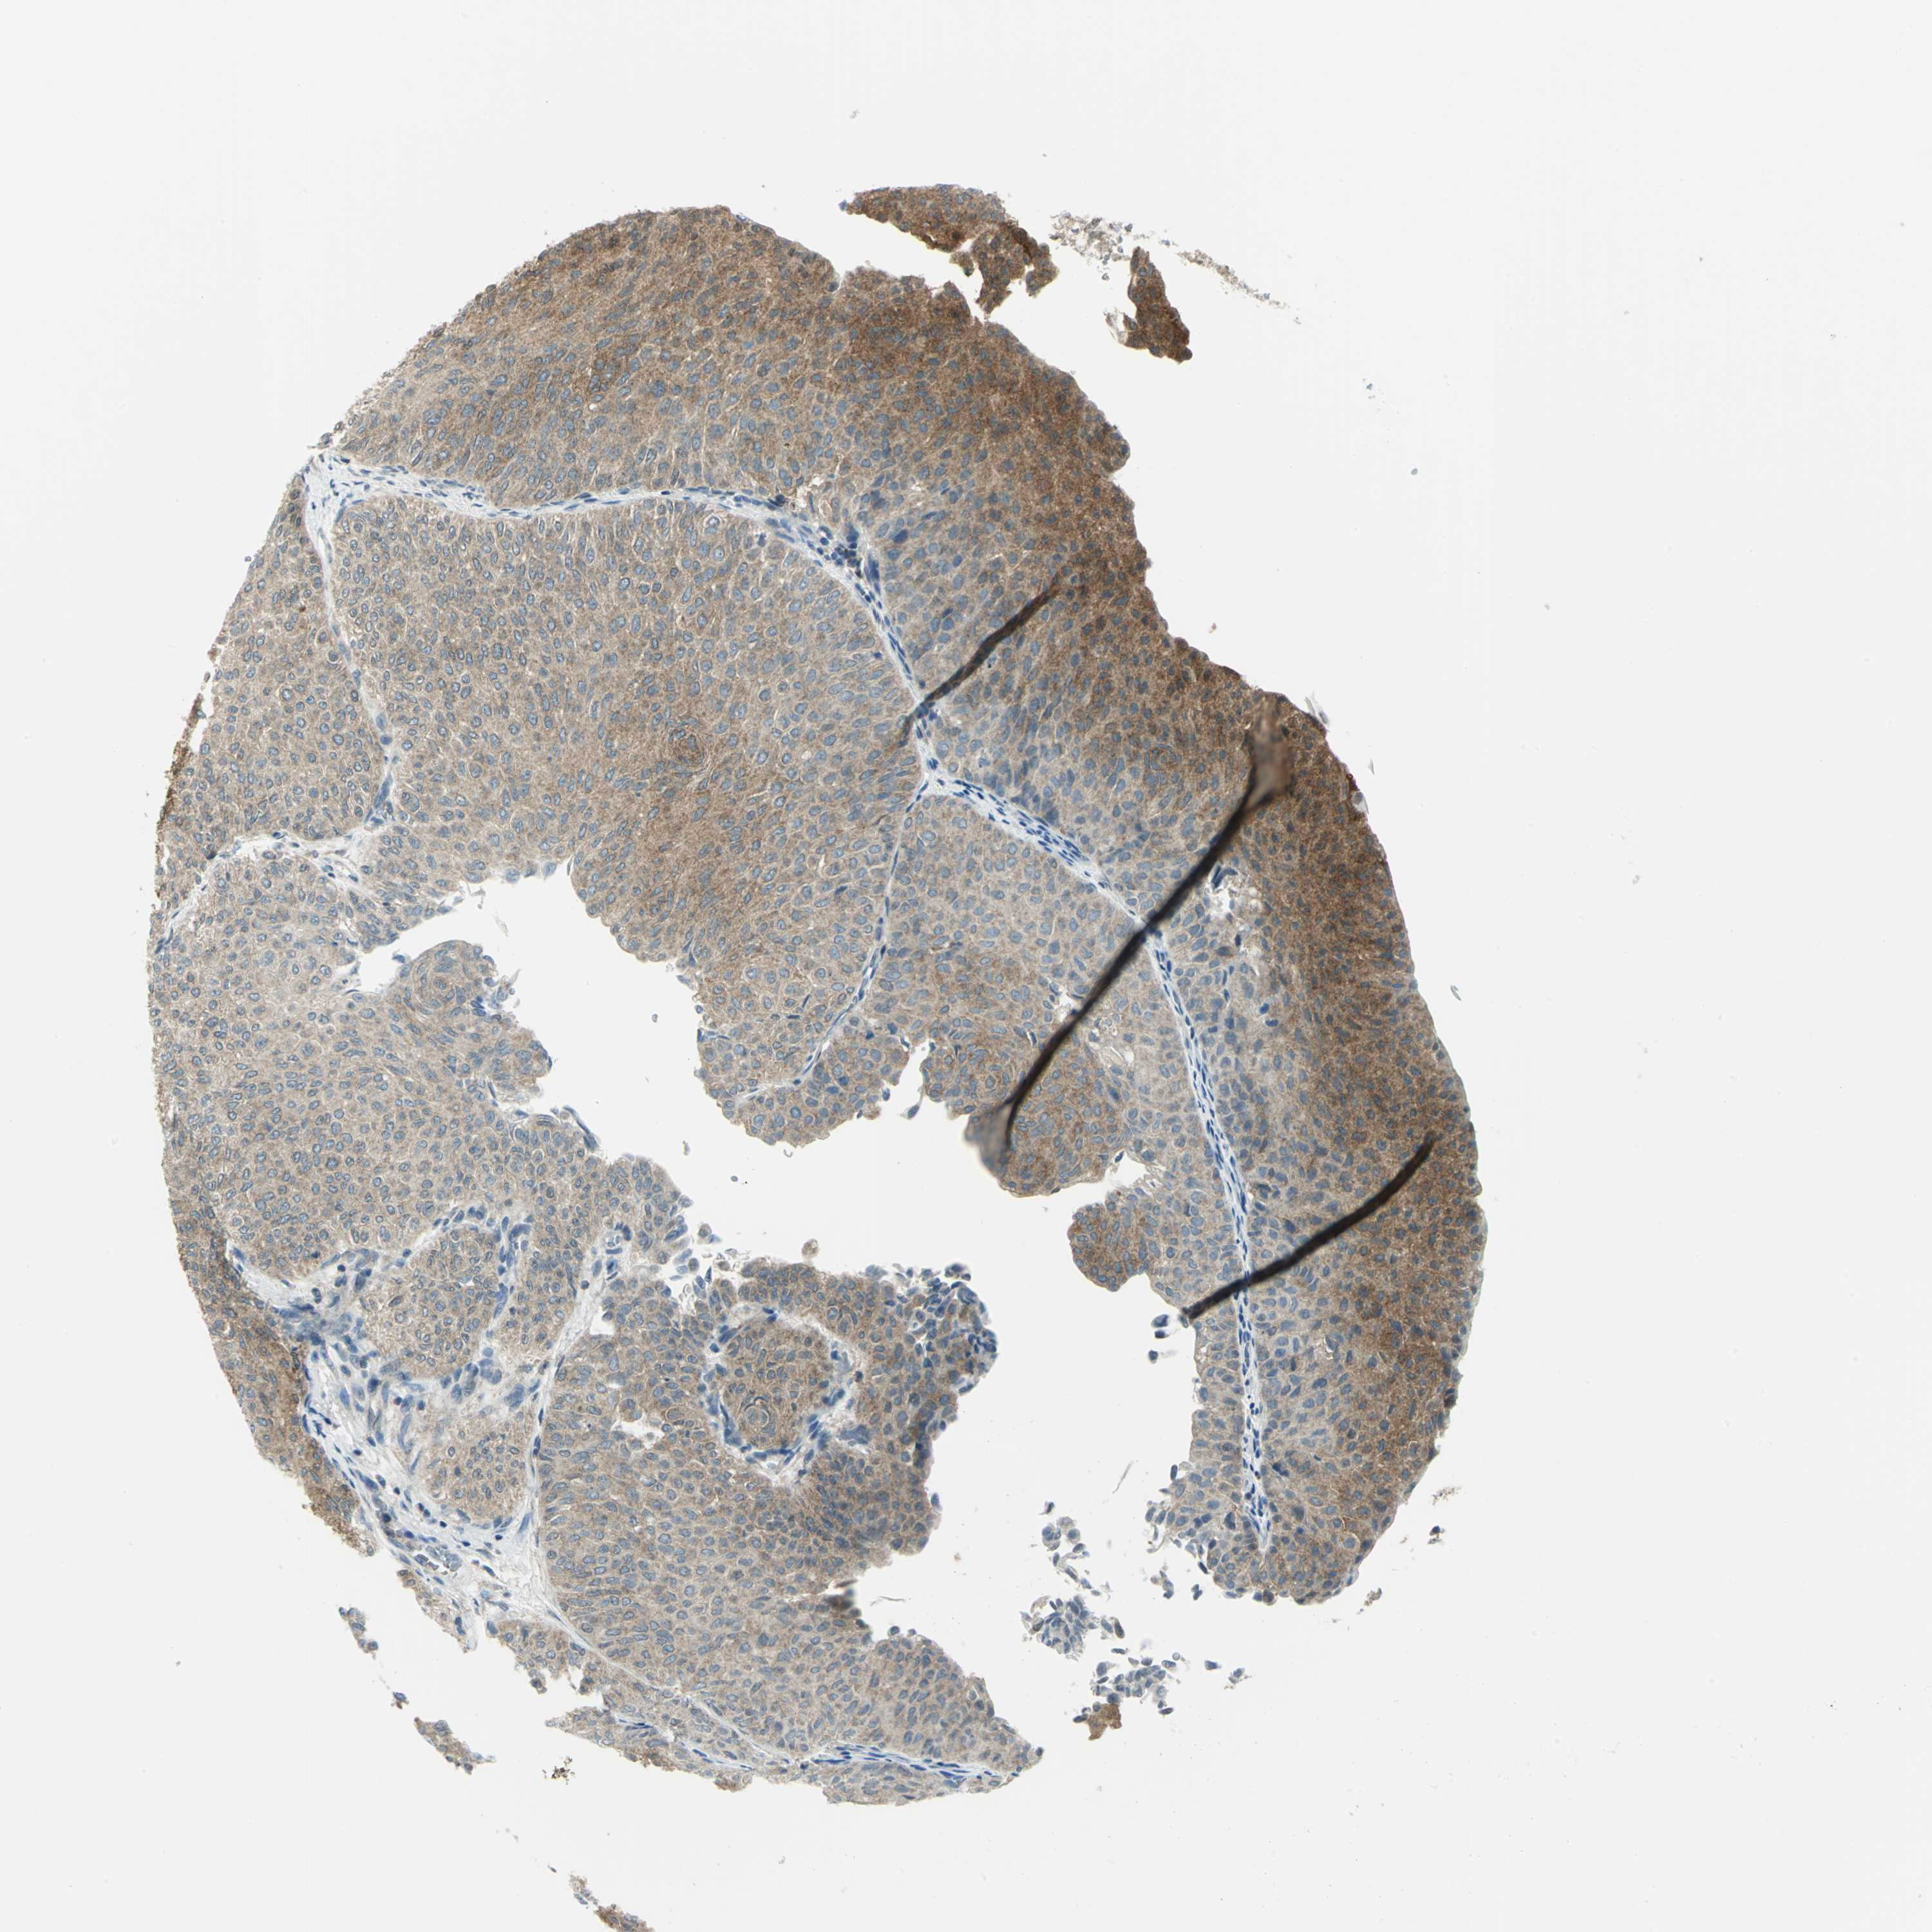

UROTHELIAL CANCER - Protein expressioni

A mouse-over function shows sample information and annotation data. Click on an image to view it in a full screen mode. Samples can be filtered based on level of antibody staining by selecting one or several of the following categories: high, medium, low and not detected. The assay and annotation is described here.

Antibody stainingi

Antibody staining in the annotated cell types in the current human tissue is reported as not detected, low, medium, or high, based on conventional immunohistochemistry profiling in selected tissues. This score is based on the combination of the staining intensity and fraction of stained cells.

Each image is clickable and will lead to virtual microscopy that enables deeper exploration of all samples and also displays staining intensity scores, fraction scores and subcellular localization as well as patient and tissue information for each sample.

Antibody HPA004177

Antibody CAB006252

Urothelial carcinoma, High grade

Urothelial carcinoma, Low grade